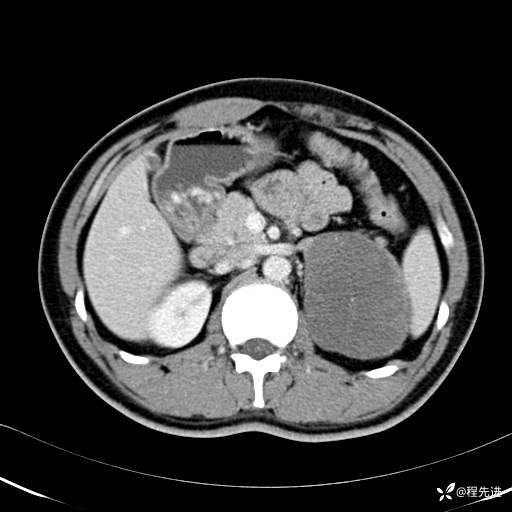

门静脉期: